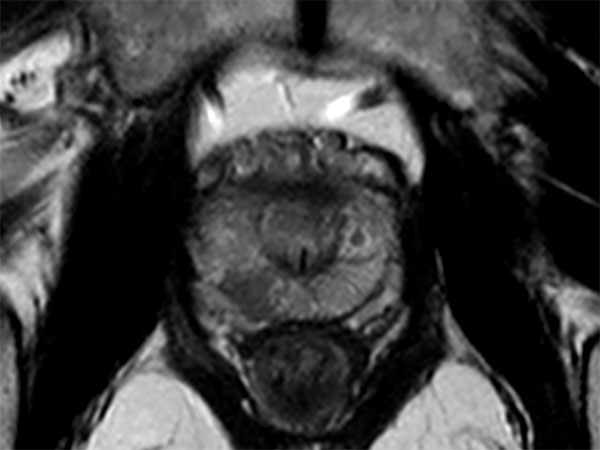

73 year old male with known prostate carcinoma. Size of 5mm, located in right posterior region. Patient is under active surveillance. Request for MR-guided prostate biopsy to re-evaluate.